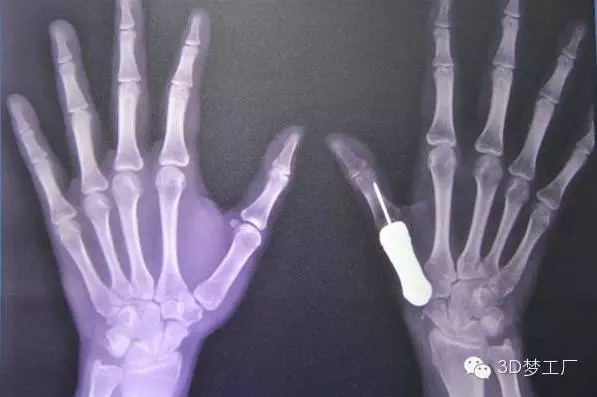

2016年1月26日,泰國(guó)曼谷Phramongkutklao醫(yī)院的醫(yī)生們宣布,他們成功用3D打印鈦金屬假體替換了一個(gè)拇指掌骨。這在世界上還是第一次。該醫(yī)院骨科主任Thipachart Punyaratabandhu博士在宣布這則消息的同時(shí)詳細(xì)介紹了他的團(tuán)隊(duì)是如何將一個(gè)3D打印的鈦金屬拇指指骨植入一位女性患者的手上,這位患者原來(lái)的指骨由于腫瘤的出現(xiàn)已經(jīng)惡化。

治療團(tuán)隊(duì)一開(kāi)始對(duì)病人健康的左手拇指進(jìn)行掃描和拍攝X光片,然后用鏡像的方法渲染出她的右手拇指指骨原來(lái)應(yīng)有的樣子,并用樹(shù)脂材料3D打印出其模型,最后用一種醫(yī)用鈦金屬鑄造出來(lái)。整個(gè)制造過(guò)程總共只用了一個(gè)星期左右,但是Phramongkutklao 醫(yī)院骨科的醫(yī)生團(tuán)隊(duì)為了研發(fā)這個(gè)3D打印拇指項(xiàng)目已經(jīng)耗費(fèi)了將近兩年時(shí)間。

據(jù)了解,手術(shù)治療是從去年6月份開(kāi)始的,當(dāng)時(shí)醫(yī)生將惡化的骨頭從病人手里取出來(lái),并等了一段日子以確保腫瘤不會(huì)復(fù)發(fā)。當(dāng)這一情況在9月下旬確認(rèn)之后,外科醫(yī)生繼續(xù)手術(shù),植入鈦金屬指骨并將其與最近的肌腱連結(jié)在一起。